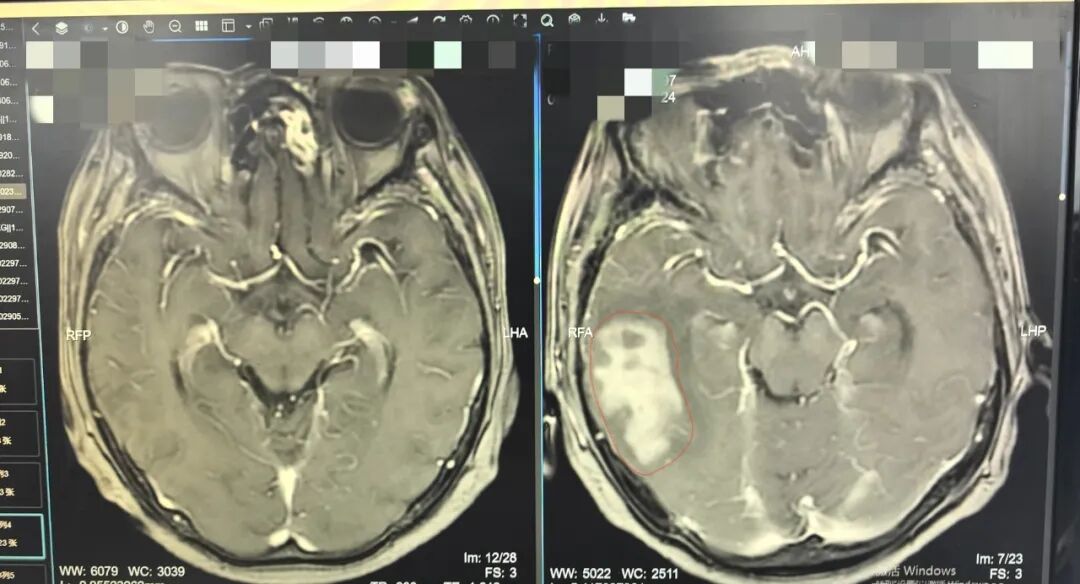

60岁女士中枢神经系统淋巴瘤,个体化综合治疗获得良好转归

病种: 中枢神经系统淋巴瘤(非生发中心亚型)

治疗方式: 立体定向活检+ 靶向联合化疗 + 全脑放疗

2025年5月,患者无明显诱因出现头痛、头晕,经检查诊断为脑内淋巴瘤。病理提示肿瘤增殖指数较高,属于预后较差的亚型,治疗挑战较大。

2. 联合治疗:采用“利妥昔单抗联合甲氨蝶呤+替莫唑胺”方案进行化疗。

3. 巩固治疗:化疗达到预期效果后,按计划进行全脑放射治疗,以清除潜在微小病灶。

💡病例小Tips: 中枢神经系统淋巴瘤治疗难度较大。通过精准活检明确诊断,再结合个体化的综合治疗(靶向、化疗、放疗),有助于实现对这类疾病的有效控制,为患者争取更长的生存期。